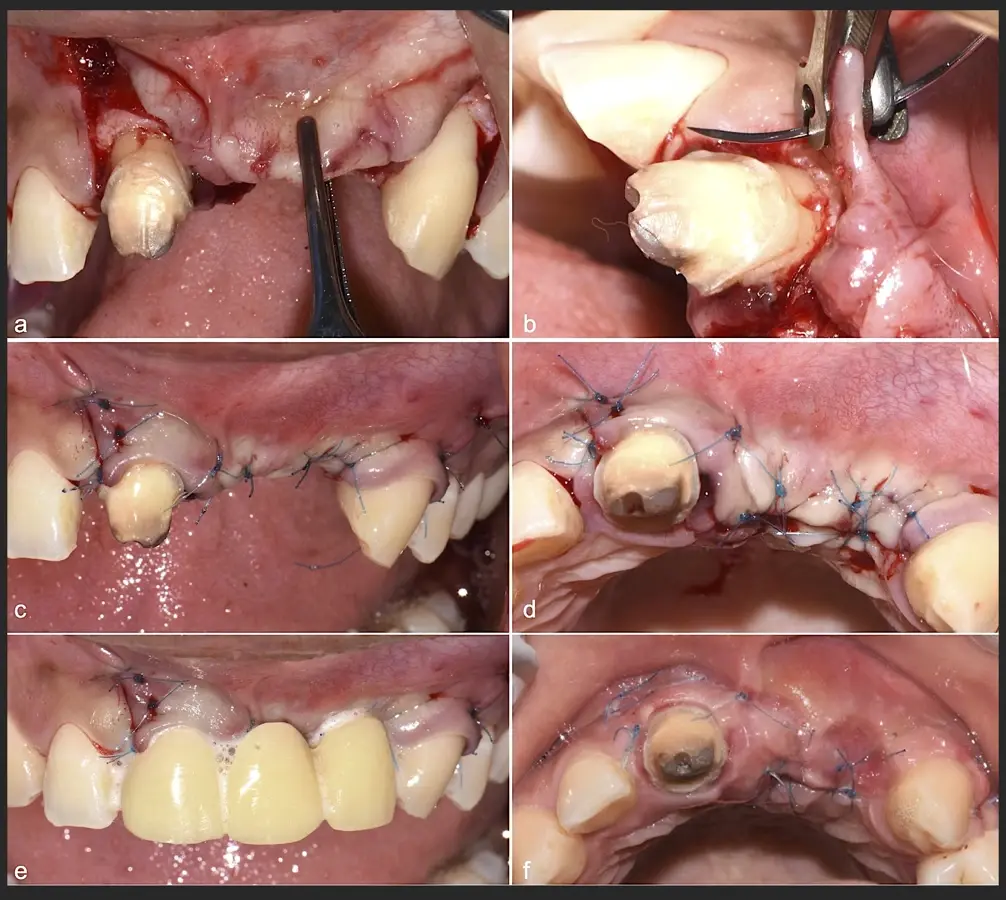

Los casos clínicos que presentamos a continuación muestran claramente las ventajas del piezoeléctrico en diversos procedimientos de terapia ósea regenerativa. En el primer ejemplo, una reconstrucción de reborde con injertos en bloque previo a la planificación de implantes dentales en un caso de edentulismo total superior con una severa reabsorción ósea. En el segundo ejemplo se utilizó esta tecnología para la reconstrucción de lechos para implantes de estructuras óseas con hueso en bloque de origen bovino y posteriormente la colocación de implantes dentales. Los dos casos son parte del capítulo 9 del libro “Cirugía piezoeléctrica: generalidades y aplicaciones clínicas”.